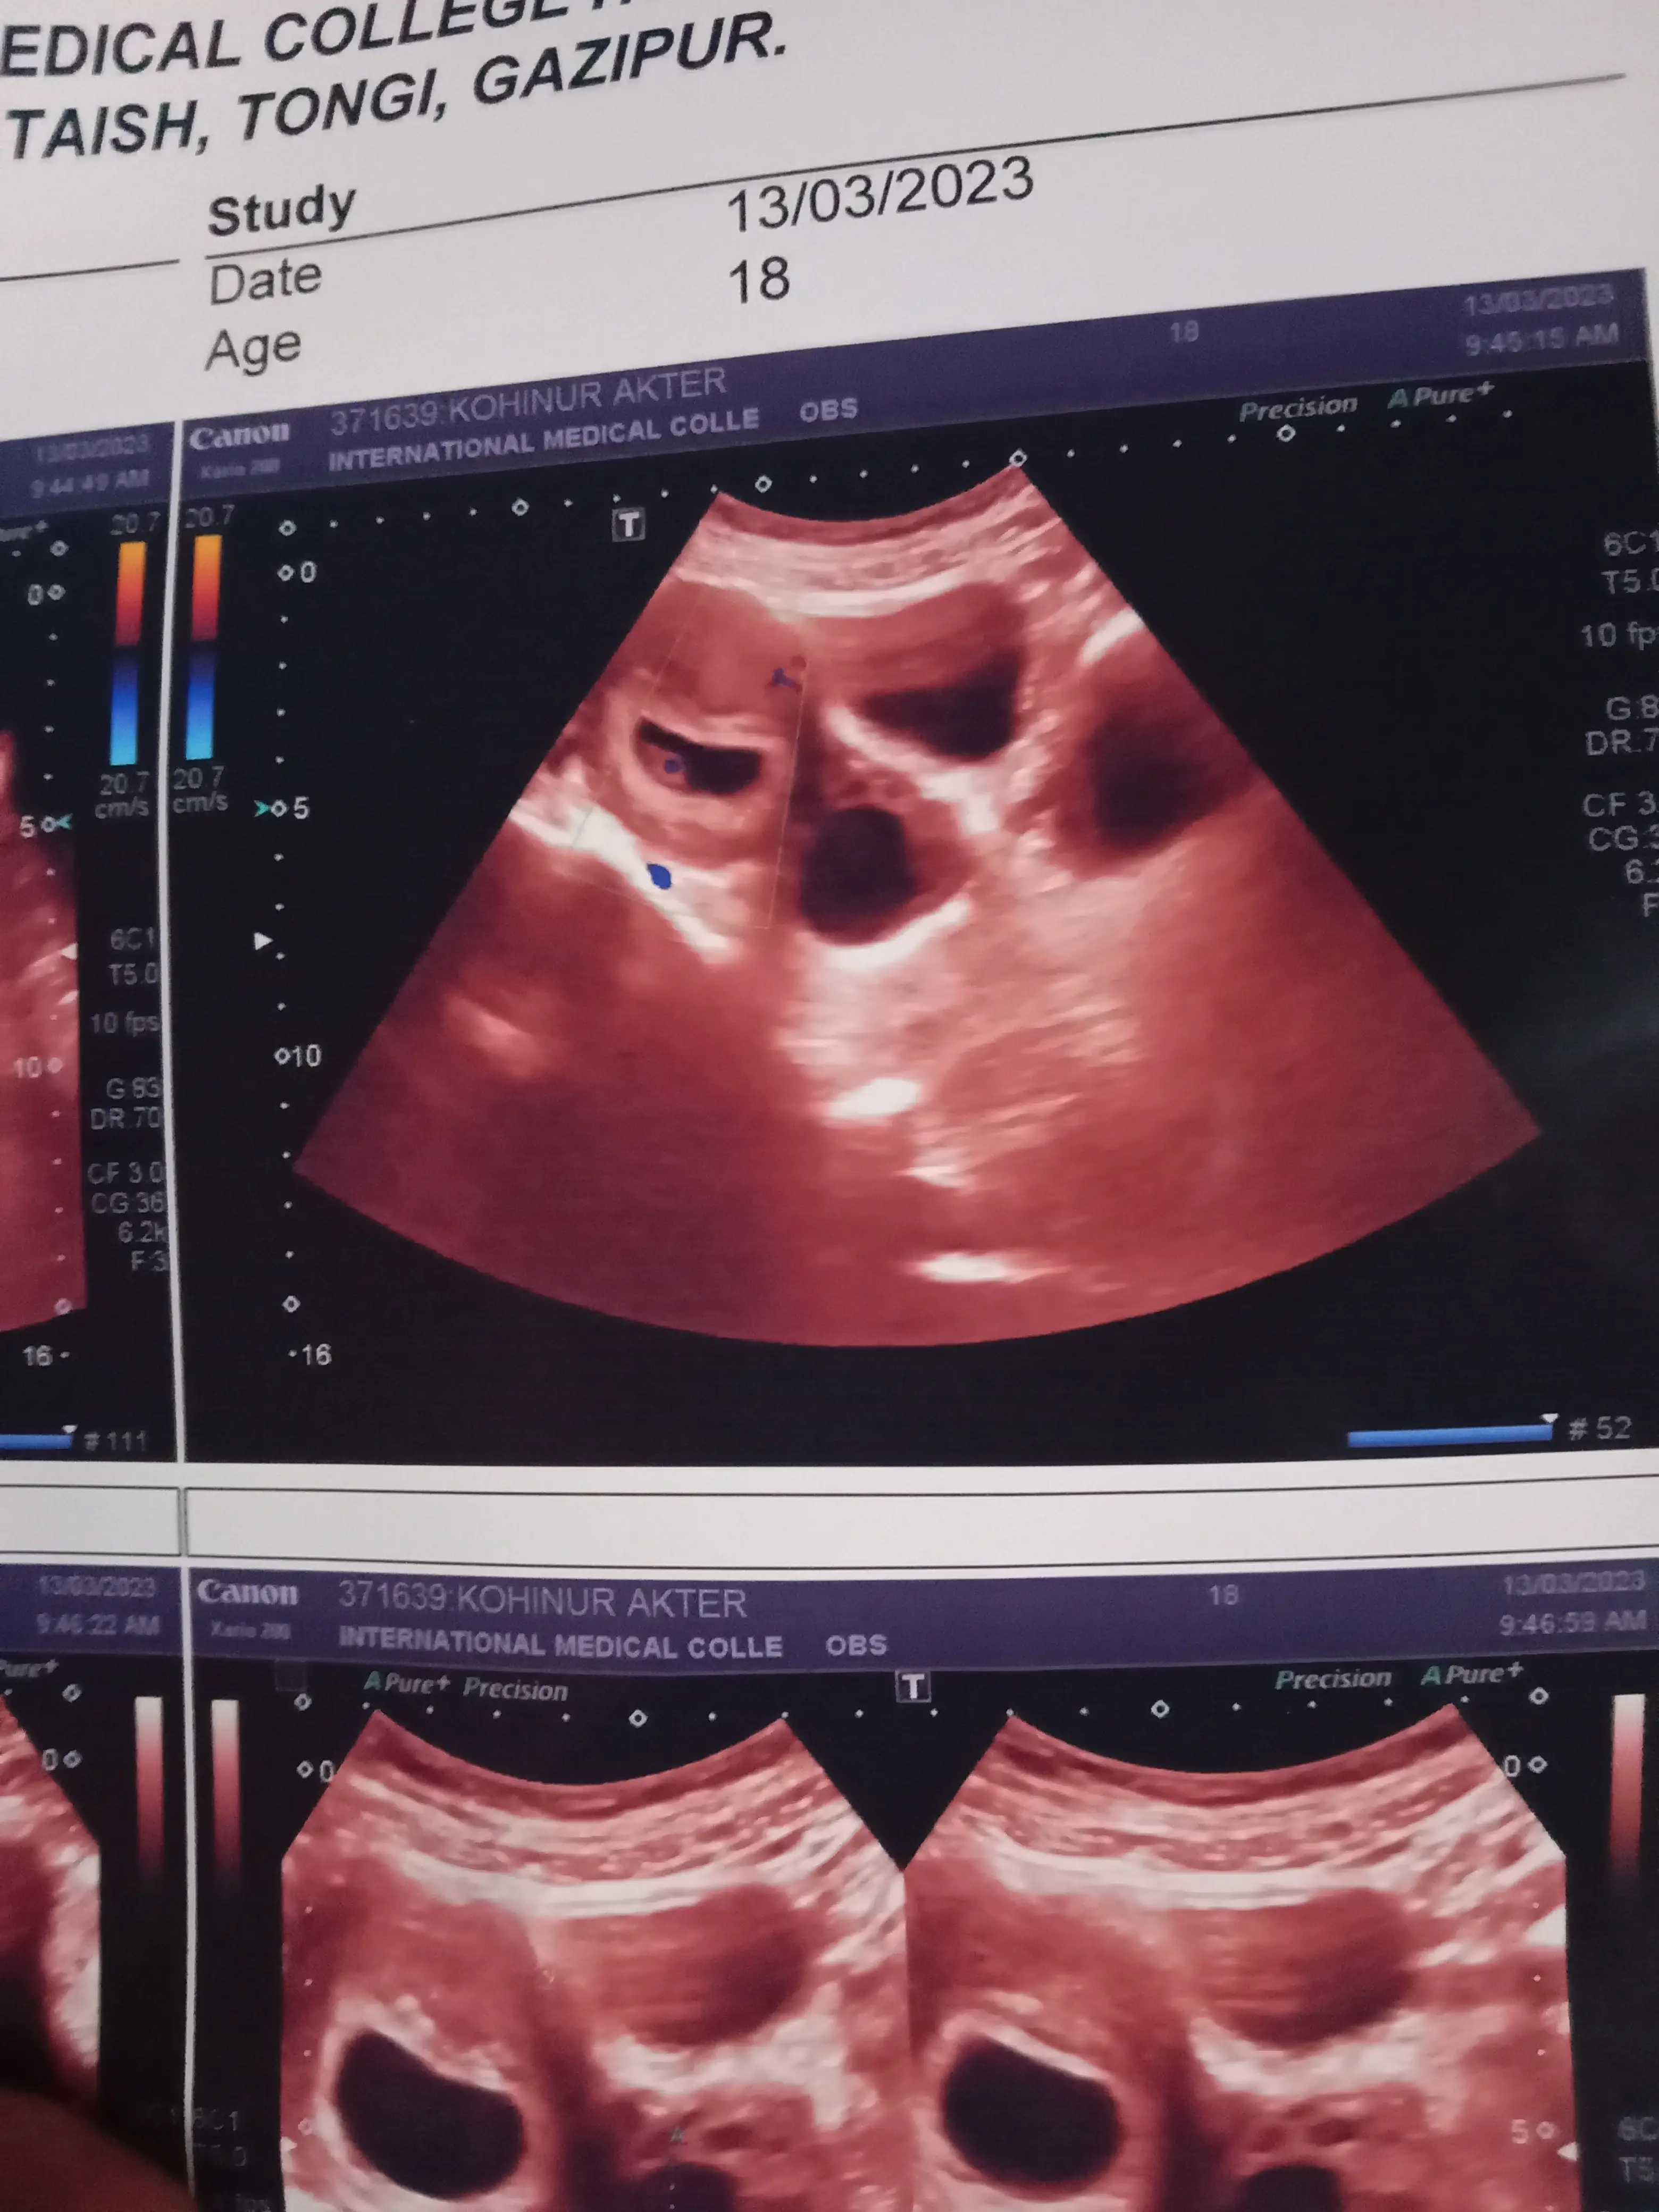

Q: Acha ekhane baby kon pase ache bojhay.....r babur ki heardbeat aschilo ...oviggo keo thakle pls bolen ....amr prothom baby onk tention e asi....pls

A: @k Apnar ripot a mone hoy baby ektar besi ei jonno jiggasa korci... See more